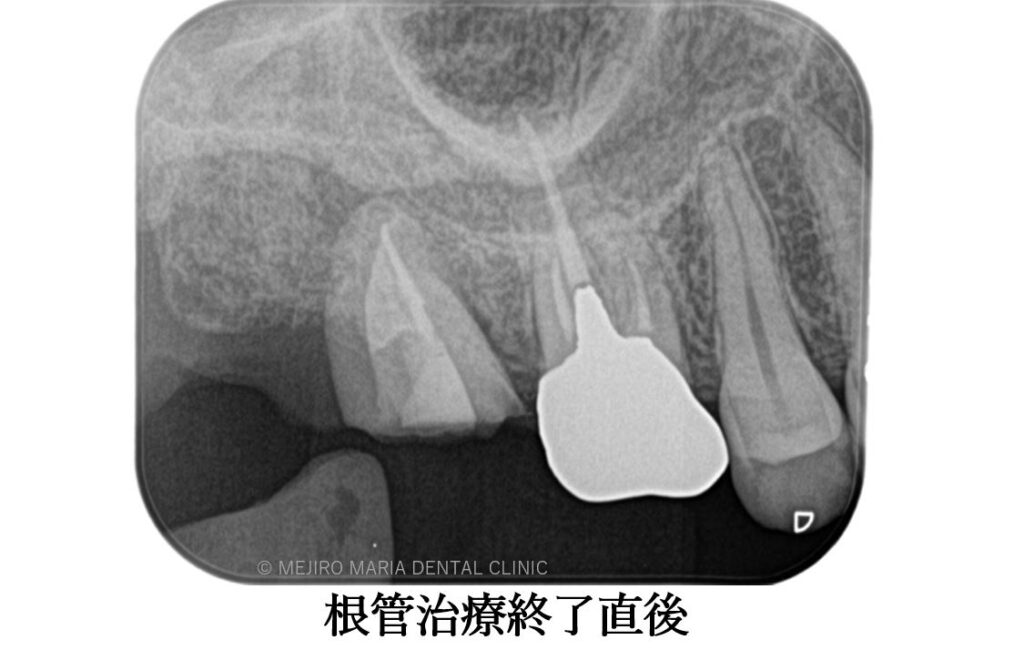

初診時には右上7番に歯髄生活反応は確認できず、歯髄壊死が起因の根尖性歯周炎と診断しました。根管治療を開始するも、歯牙は既に破折しており患者様には抜歯することをおすすめさせていただきました。

左上の親知らずを抜歯後、すぐに右上7番部位に移植を施し2週間経過後に精密根管治療を行いました。

精密根管治療終了後3ヶ月で、術前に確認できた病変の縮小は顕著に確認でき、予後経過は良好と判断します。今後、最終補綴処置に移行し経過観察を行っていきます。